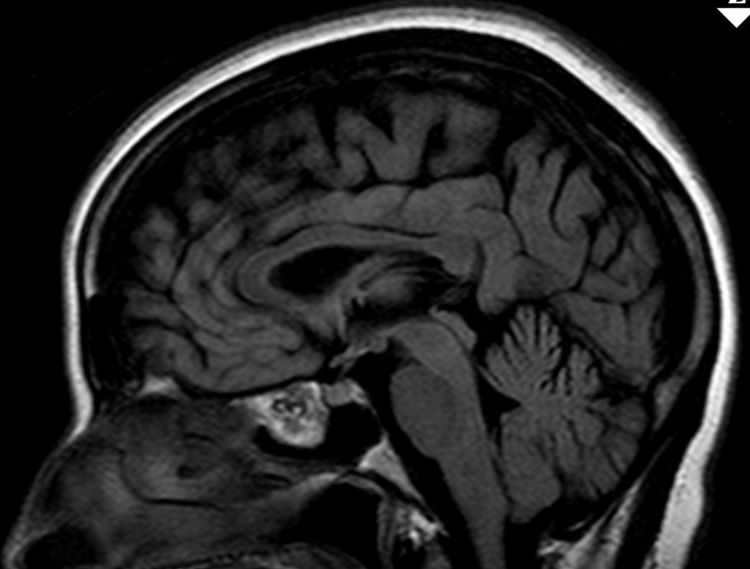

50-jährige Frau (I251), die vor 7 Jahre ein Mammakarzinom (rechts oben außen, T1c No Mo, invasiv NST hatte. Bisher metastasenfrei. Jetzt vor der Sella, in der linken Keilbeinhöhle eine z.T. verkalkte Raumforderung. 2 Jahre unverändert kontrolliert.